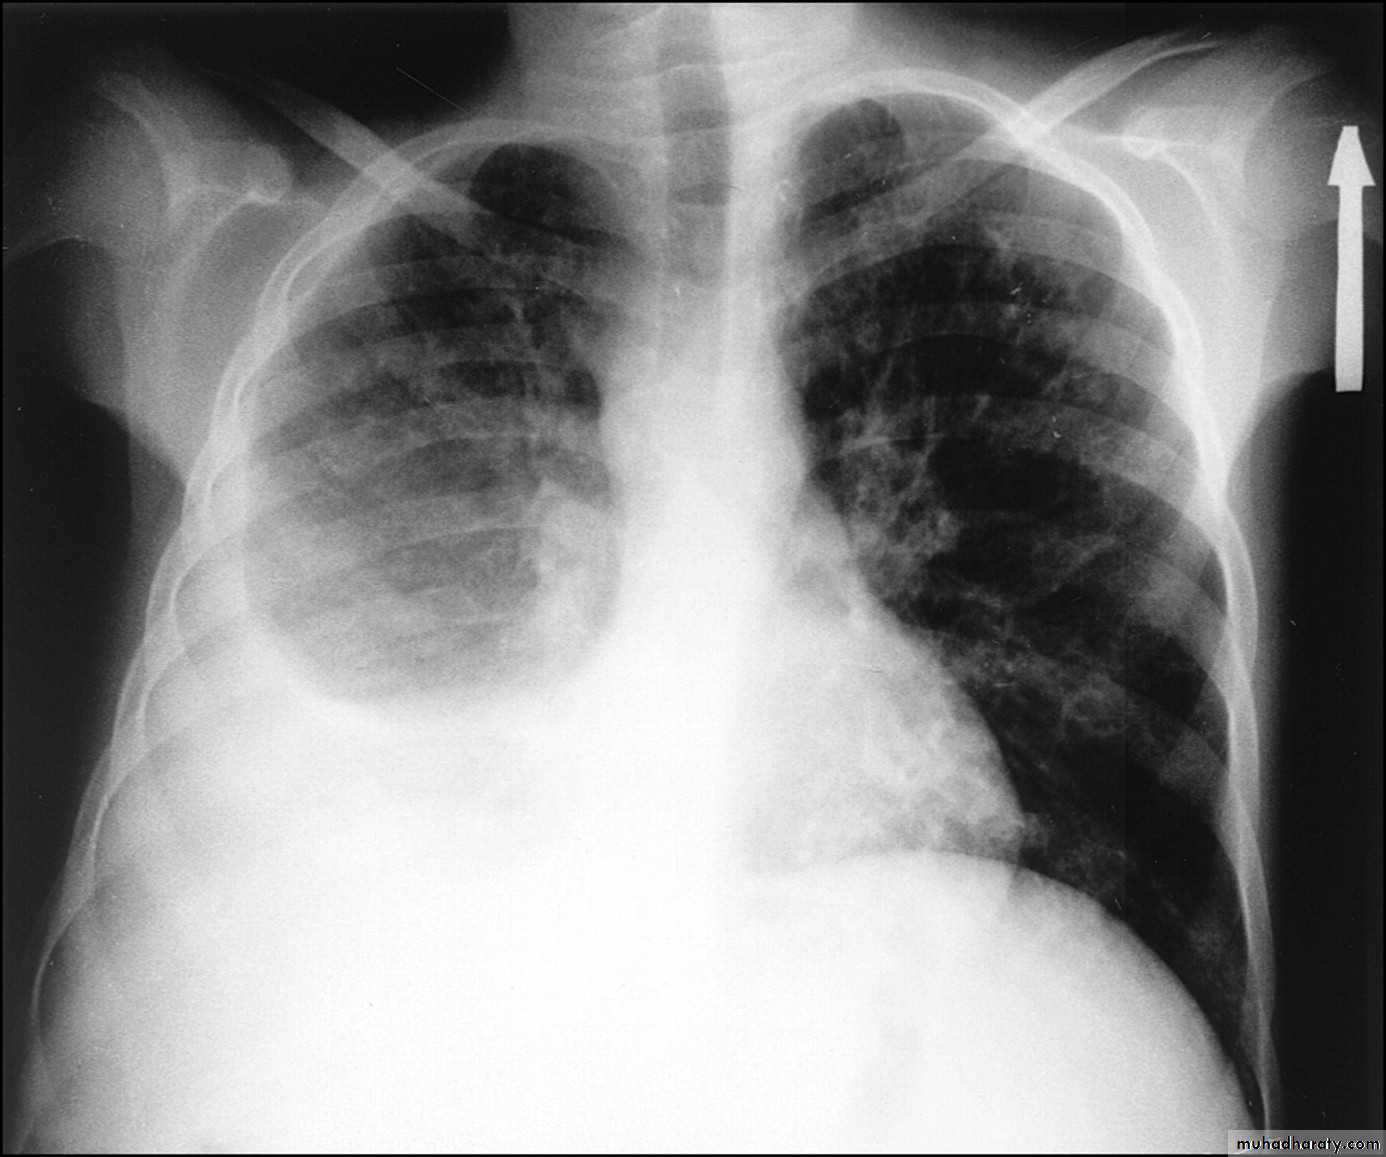

Post primary TB broncho pneumonia cotton wool signBilateral patchy opacities of the upper lobes of the lungs, cotton wool sign.

61.post primary TB notice upper apical Broncho pneumonic shadow

Bilateral Patchy opacification of the lungs involving upper zones, a cavity can be seen in the right uper lobe( 3rd photo)bronchopnemonia

Bilateral patchy opacity mainly involving lower lung zonesprimary TB bronchopnemonia

Bilateral patchy opacity mainly involving upper lung zonesBoth of them have similar appearance of broncho pneumonic shadow